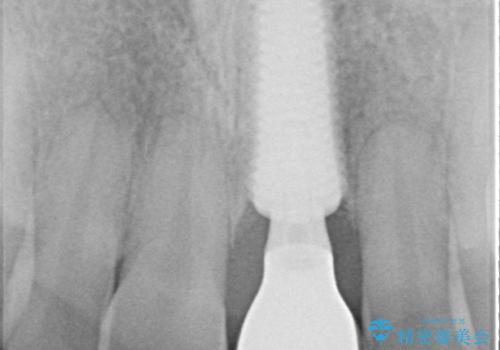

- 前歯のインプラント治療を希望して来院された患者様です。

小学生の時に前歯を殴打したとのことで、歯根が吸収してしまい、抜歯が必要と判断されました。

抜歯、インプラント埋入、仮歯の装着が同時に可能な1DAYインプラントを行いたいところでしたが、吸収による歯肉の炎症が著しいため、抜歯後に炎症が治まるまで待機し、極力早期にインプラント埋入を行うこととしました。